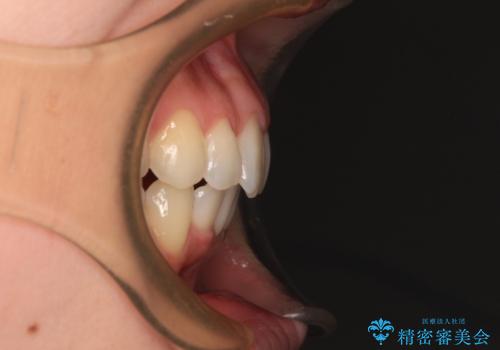

- 前歯のデコボコで前方に出ていることを気にして来院された患者様です。

上顎前歯が捻れて前方に飛び出しており、下顎前歯もそれに沿うようにデコボコとなっていました。

IPR(歯と歯の間を削る処置)によりスペースを獲得して上下顎前歯のデコボコを改善し、飛び出している前歯が引っ込むように設定し、インビザラインにて矯正治療を行うこととしました。